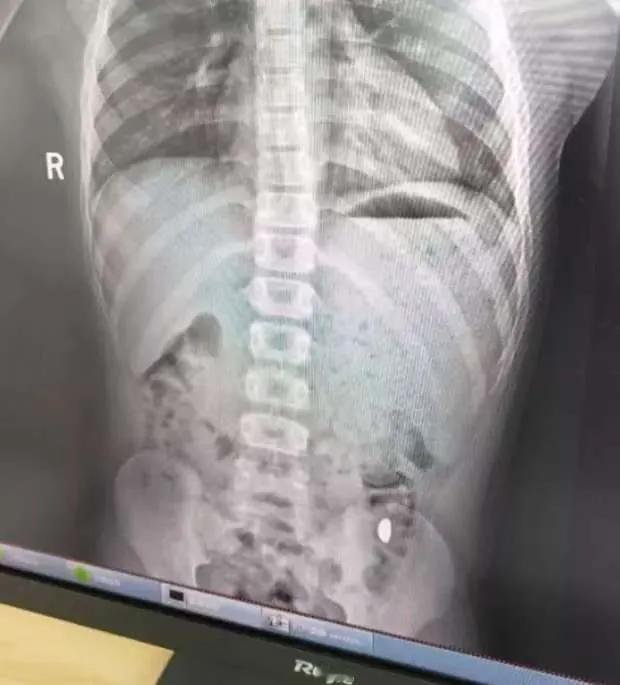

金豆被娃吞,妈妈蹲厕“寻宝”:藏在哭笑不得里的安全课 “这哪是养娃,是养了个‘吞金兽’啊!”10月27日,江苏昆山的纪女士对着马桶里的“战利品”长舒一口气——那颗让全家悬心3天的10克金豆,终于随着孩子排便“完璧归赵”,而这背后的折腾,全因她一句无心的话。 10月17日,纪女士花万元网购的投资金豆到货,拆快递时特意跟11岁的儿子念叨:“这颗‘小金球’值好多钱,是妈妈攒的应急钱。”她没料到,这句“强调”竟让儿子记在了心里。22日午后,儿子趁她收拾家务,偷偷把金豆拿进房间把玩,还突发奇想“试试舌头能不能顶住它不掉”,结果一个吞咽动作,金豆直接滑进了肚子。 “当时他举着空手心跑过来,脸都白了:‘妈,金豆被我咽下去了!’”纪女士回忆,起初以为孩子在开玩笑,直到翻遍房间找不到金豆,才慌了神。想起之前刷到“纯金无毒性、圆润异物可自然排出”的科普,她没敢盲目催吐,却架不住金豆价值近万元——按10月28日银行金条946元/克的价格算,这颗金豆足足值9460元。 接下来的3天,纪女士的生活围着“找金豆”转:每天早晚盯着儿子排便,连厕所都不让出,反复叮嘱“这屎比玩具贵,丢了就亏大了”;排便后蹲在马桶边仔细翻看,生怕看漏一丝金光。直到10月26日下午,孩子排便时突然喊“妈,金光!”,她冲过去一看,那颗光滑的金豆正躺在粪便里,完好无损。 虽然虚惊一场,但纪女士把经历发到社交平台后,立刻引发50多万家长共鸣——有人晒出孩子误吞硬币、纽扣的经历,有人吐槽“越强调‘贵重’,孩子越好奇”。正如大皖新闻报道中,昆山市第五人民医院儿科医生提醒的:“家长别在孩子面前过度强调物品价值,反而会激发探索欲;小物件、贵金属要锁进高处柜子,误吞后别盲目等待,需及时就医排查风险。” 这颗“闯祸”的金豆,与其说是一场乌龙,不如说是给所有家长的安全警示:孩子的好奇心从无对错,但成年人的“收纳疏忽”和“无意引导”,往往会让小物件变成大隐患。把贵重物品藏好、把安全常识说透,才是避免“吞金”这类哭笑不得的事,最靠谱的办法。 本文根据大皖新闻相关信息创作,旨在提醒家长,增强安全意识,勿把细小物件让孩子把玩 网络截图